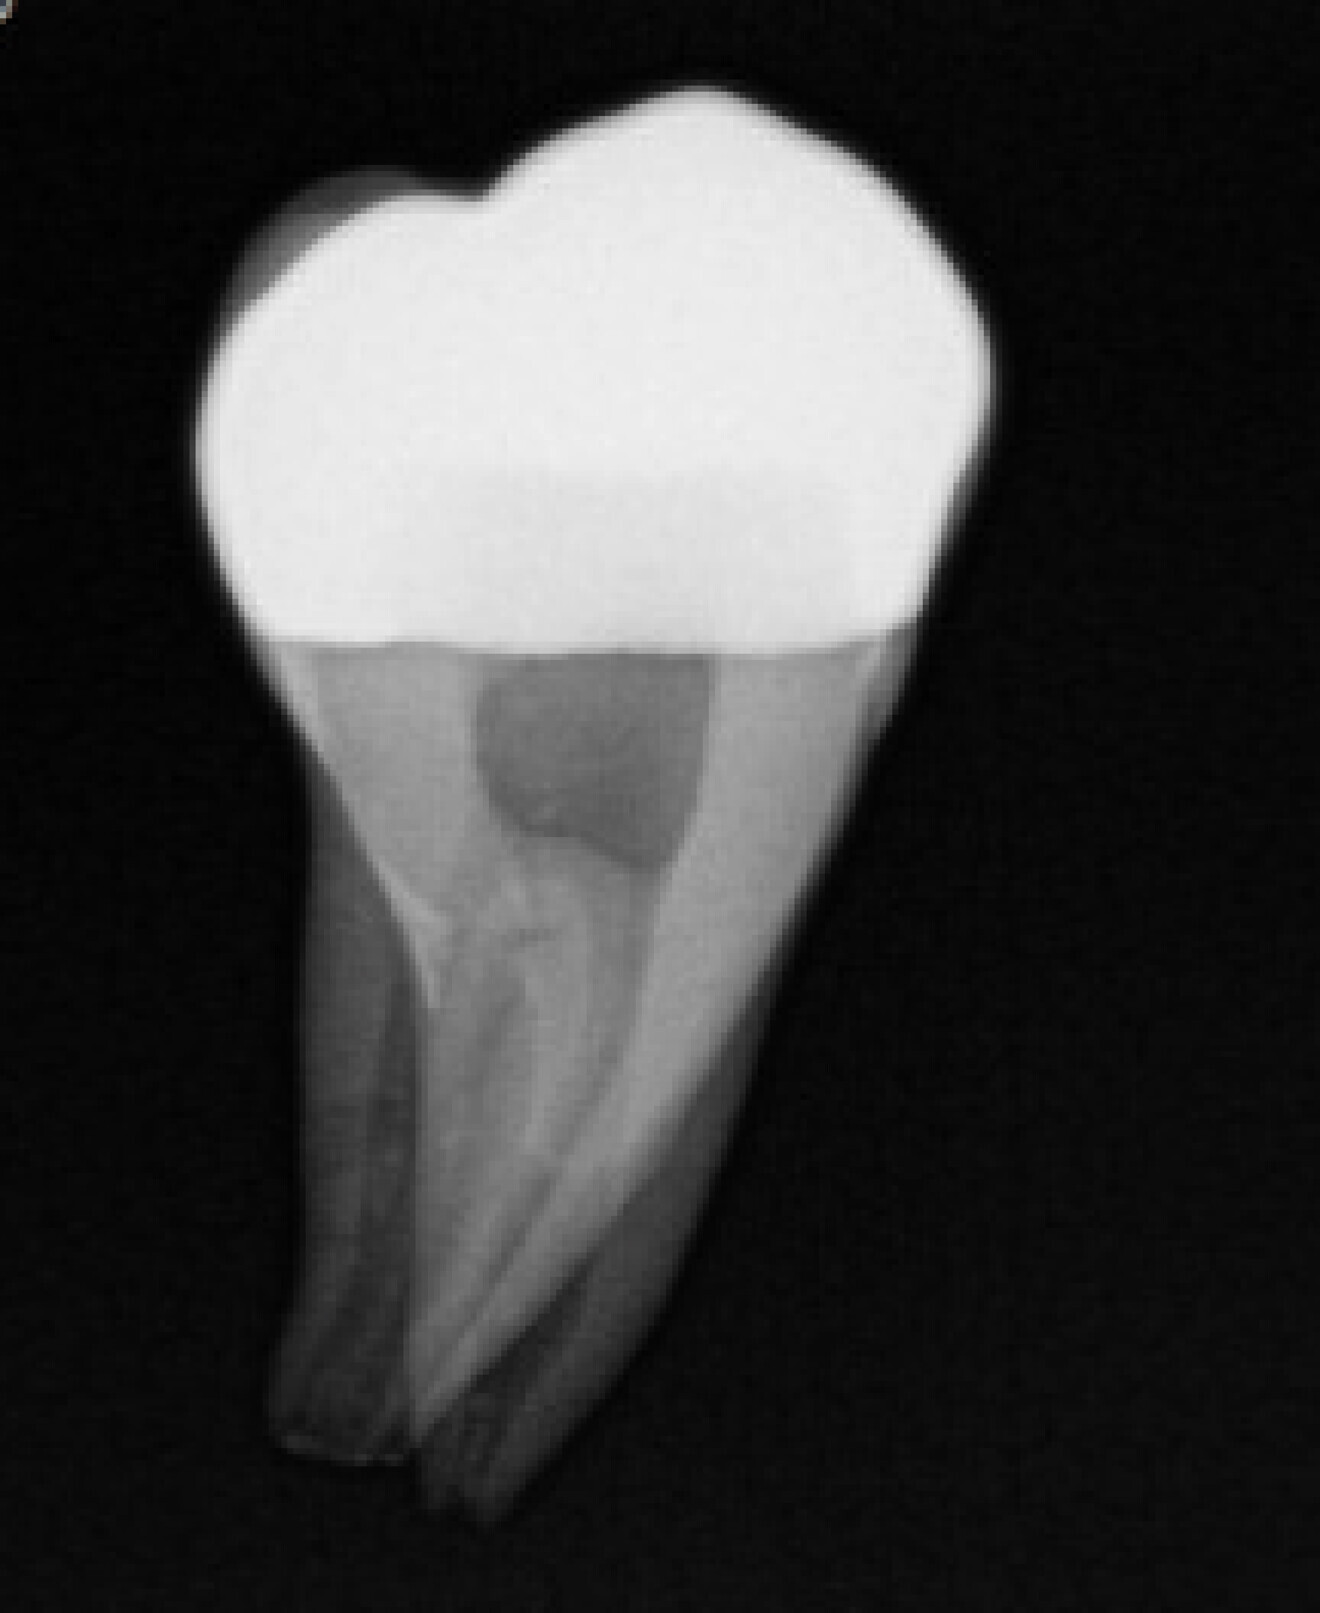

Fig. 9: Radiograph of cemented onlay.

Fig. 10: Radiograph of cemented onlay.

The digital scanner provided an STL file of appropriate resolution for metal additive manufacturing or 3D printing. The indirect onlays were successfully printed in cobalt–chromium with the morphology, dimensions and fit that were clinically acceptable for cementation. Cementation was completed without issue and with suitable retention, similar to previous investigations.6 The marginal adaptation was generally acceptable, except for one area, owing to an open margin. The surface finish was generally acceptable, but could be improved in some places, especially on the occlusal surface.